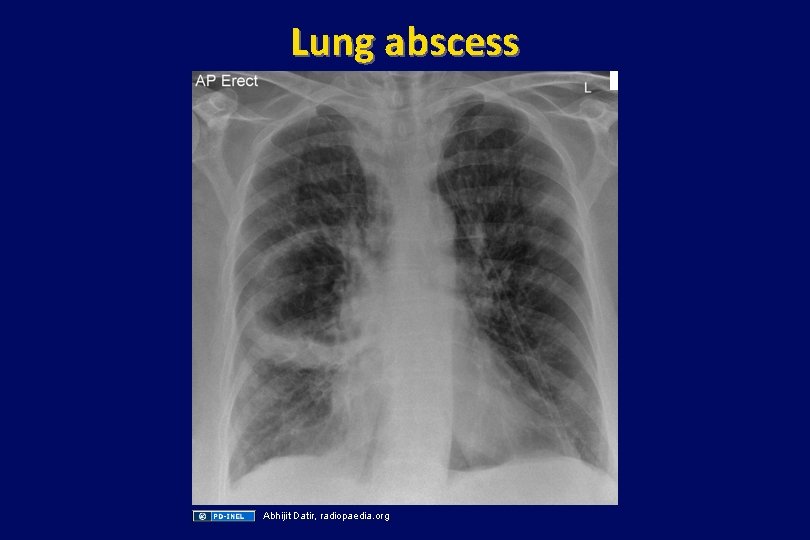

Case (continued) • He is admitted and started on ceftriaxone for probably pneumonia • Later the same night, the patient starts coughing copious amounts of grayish, putrid sputum that can be detected on the next ward. • A chest xray is taken, and treatment with metronidazole is added.

Lung abscess Abhijit Datir, radiopaedia. org